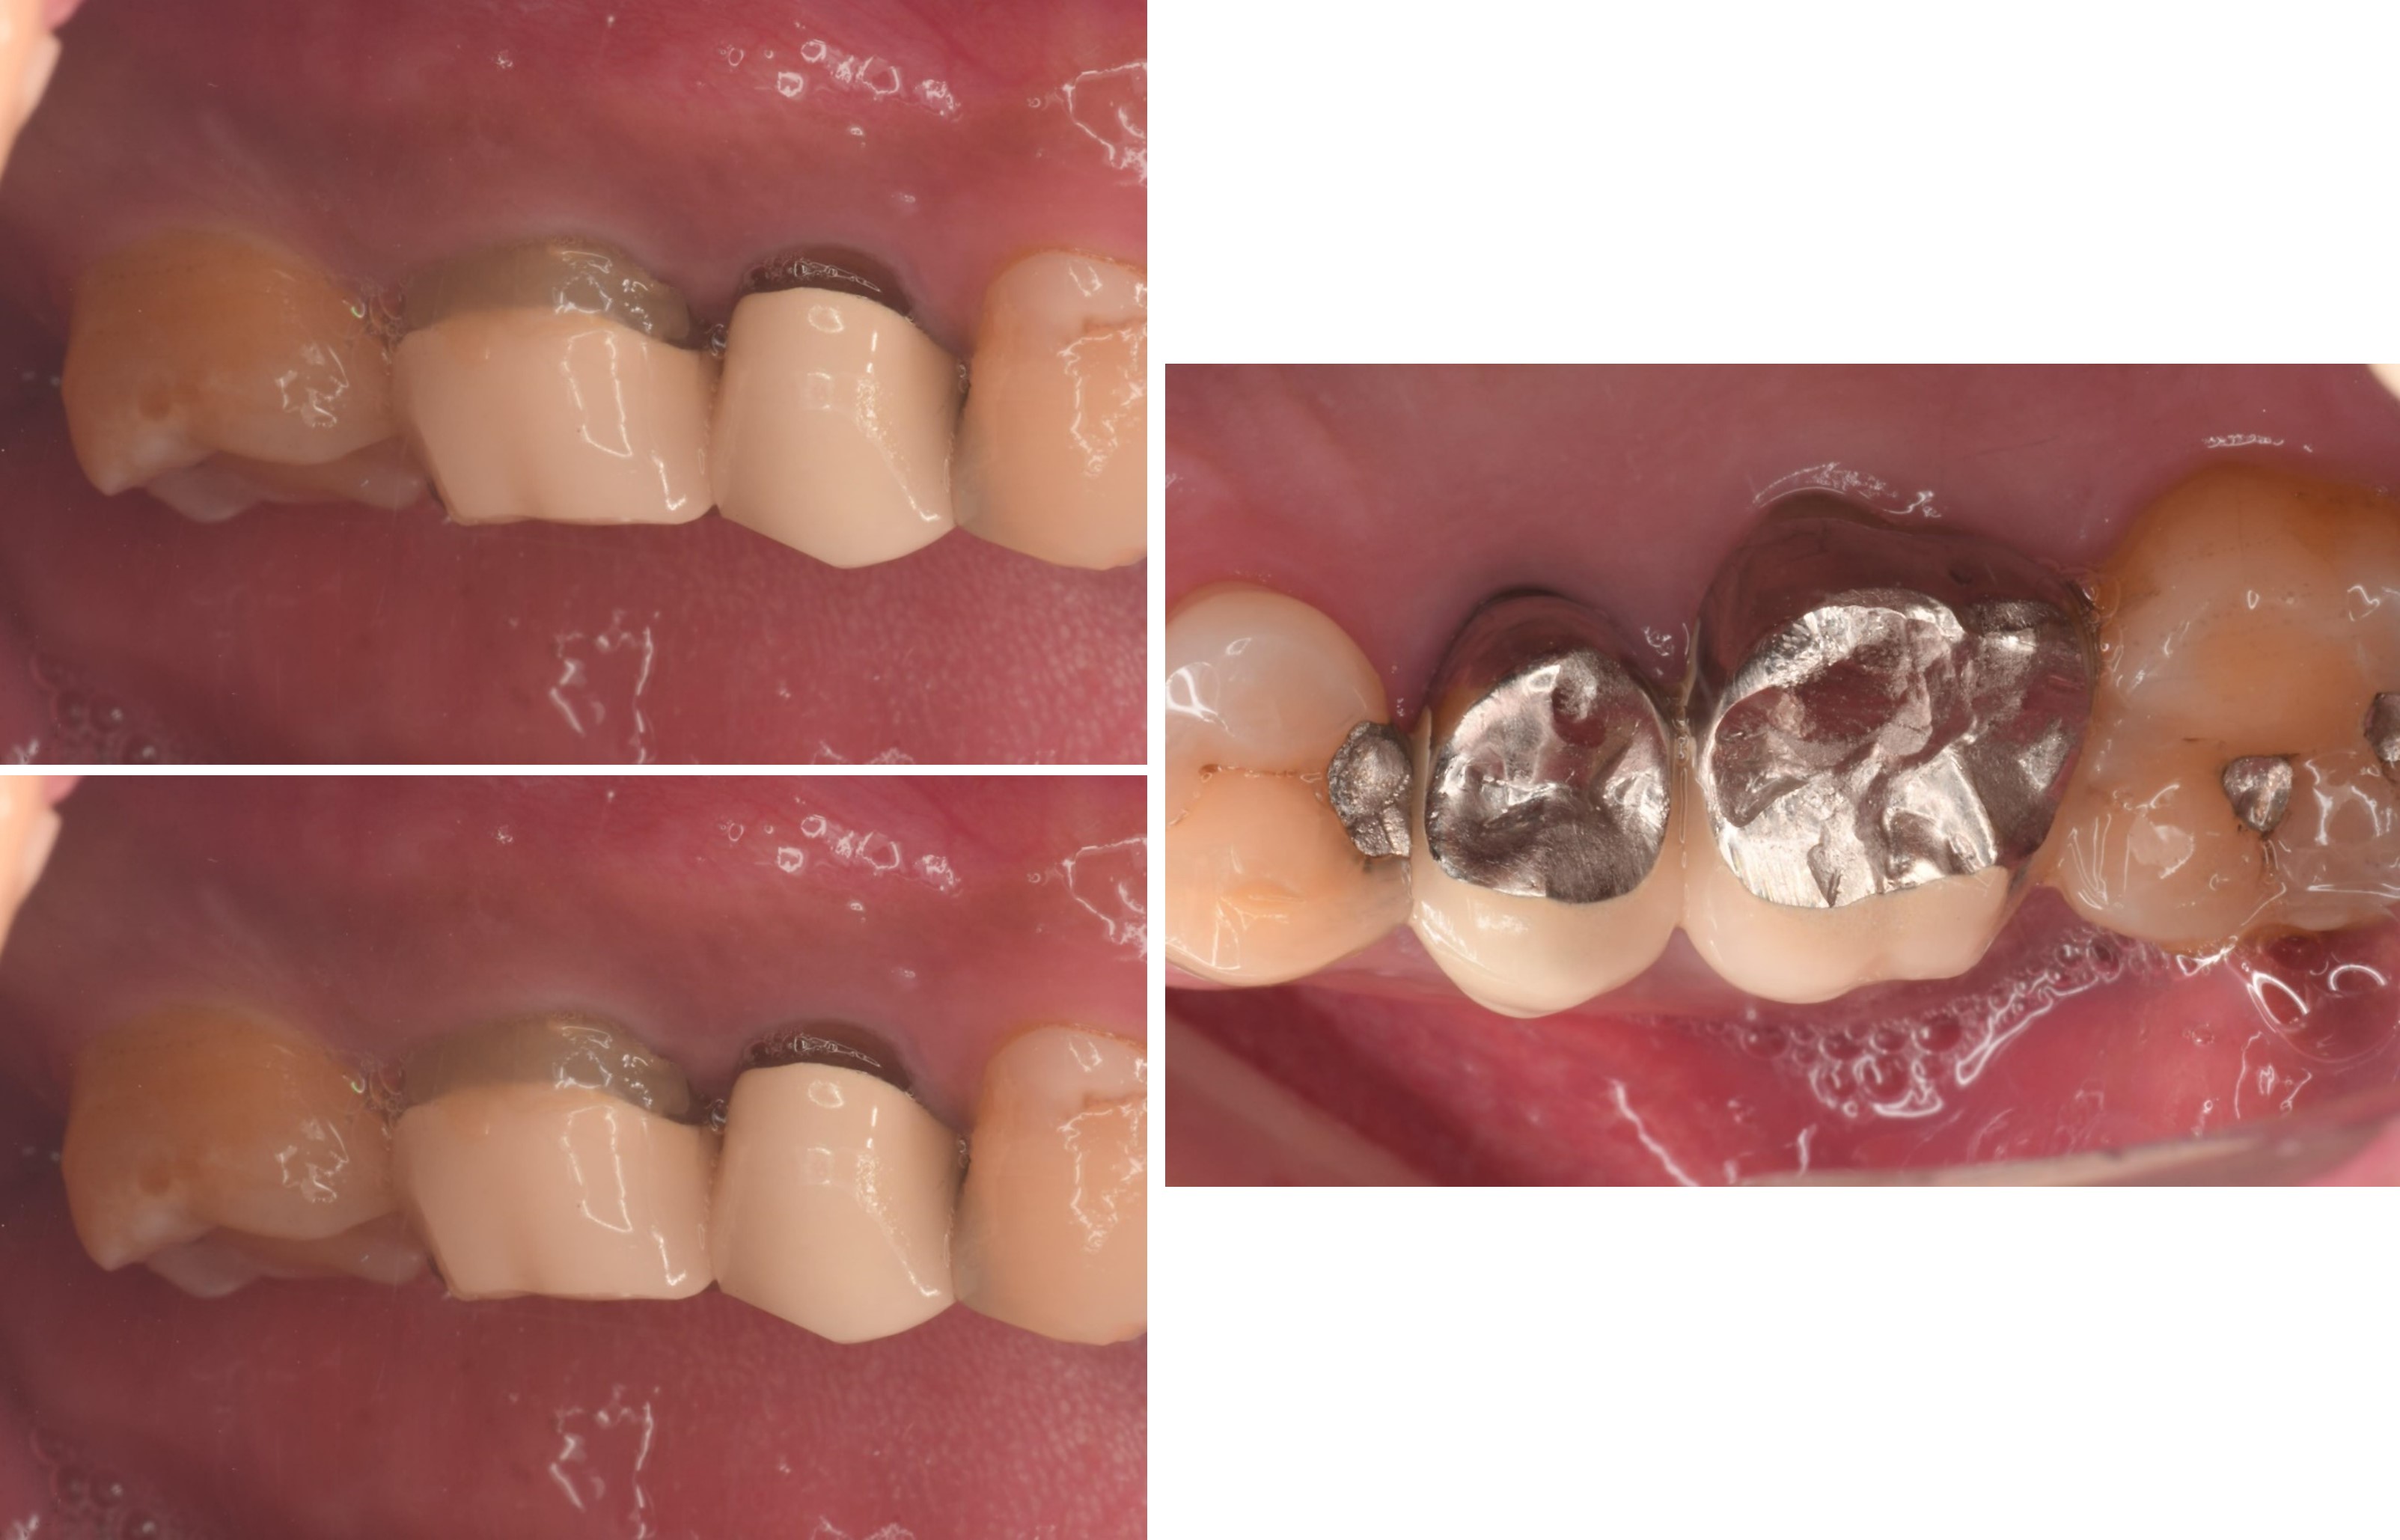

治療前,右上第一大臼齒疼痛

膺復前評估牙齦、牙齒狀態